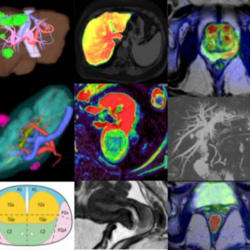

Imágenes Abdomino Pelvianas